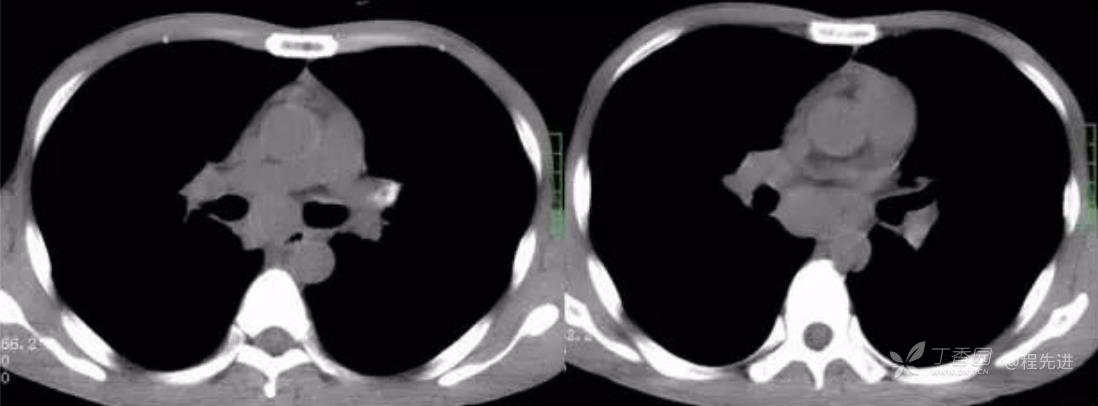

静脉期

动脉期CT值32HU,静脉期CT值54HU

左动脉期,右静脉期